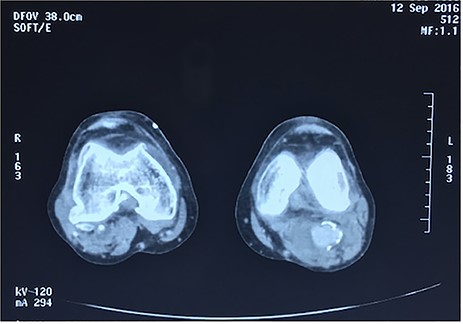

Approval for retrospective reports is not required by our institutional review board. This study is in accordance with the principles of the Declaration of Helsinki. A 77-year-old man with multiple comorbidities, including coronary vascular disease, hypertension, dyslipidemia, previous right carotid endarterectomy, and endovascular aortic repair (in 2011), was referred to our unit for evaluation of a retropopliteal pulsatile mass. He had undergone infra-popliteal stenting 18 months earlier, to treat peripheral arterial disease with severe left claudication. The procedure was performed at another vascular institute, and the stent type was unknown. Physical examination revealed the presence of a femoral and popliteal pulse and the absence of tibial pulses; at admission, the ankle–brachial index was 0.8. According to the patient, he had noticed the mass in the last 2 months prior to admission, but the absence of pain delayed his presentation to the hospital. An ultrasound scan was performed on admission and revealed a large popliteal pseudoaneurysm with normal flow present distally, and fracture of the stent was confirmed by computed tomography, which also detected a 4.2 cm dilatation of the left popliteal artery (Figs 1–3).

Angiotomography revealed fracture of a stent deployed in the popliteal artery and a pseudoaneurysm formation of size 4.2 cm at the part of stent fracture.